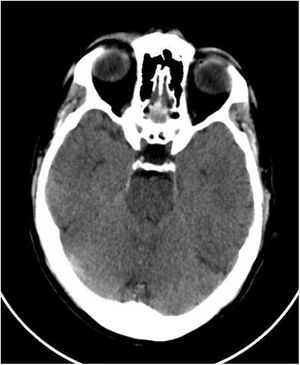

Se trata de un varón de 61 años sin antecedentes personales, y no vacunado frente al SARS-CoV-2, que comenzó a consumir por voluntad propia de forma diaria dióxido de cloro con la creencia de prevenir la infección. A las 2 semanas presentó cuadro encefalopático de instauración progresiva con bradipsiquia, desrealización, irritabilidad e inquietud. A la exploración física se evidenció deshidratación cutáneo-mucosa. Se realizó tomografía computarizada (TC) craneal que reveló edema cerebral e hipertensión intracraneal idiopática (fig. 1). Se realizaron fondo de ojo y punción lumbar resultando normales. En analítica sanguínea se objetivó: sodio 112mEq/l, cloro 77mEq/l, osmolaridad plasmática 230mOsm/kg y ácido úrico 2,2mg/dl, excreción fraccionada de úrico (FEUa) al ingreso: 15,4% y tras 72h con normalización de la natremia, FEUa: 11,4%. En gasometría venosa se objetivó pH 7,42, bicarbonato (HCO3) 21mmol/l, CO2 42mmHg. Resto sin hallazgos a destacar. En análisis urinario: sodio 72mEq/l, potasio 30mEq/l, cloro 55mEq/l, ácido úrico 15,4mg/dl y osmolaridad 224mOsm/kg. Se retiró de forma inmediata el dióxido de cloro iniciándose tratamiento para reposición hidroelectrolítica según déficit de sodio progresivamente, con restablecimiento paulatino del estado neurológico y normalización de parámetros analíticos (tabla 1). Se realizó un diagnóstico diferencial de otras posibles causas de hiponatremia.